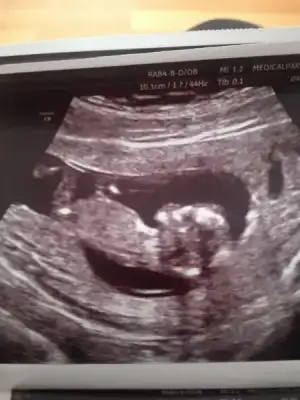

Dr tahmin etti kızlar :) sizce ne benim kuzum:)